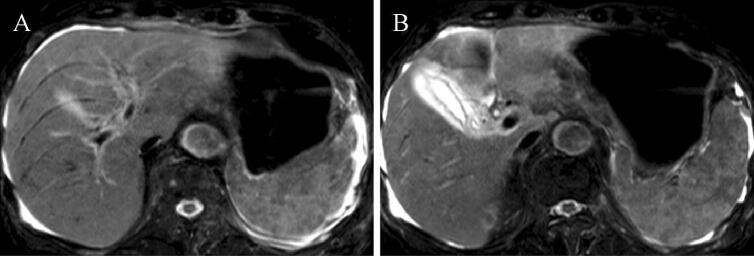

Fig. 3.

An MRI examination revealed thickening of the gallbladder wall (a) and ascites (b)

An 87-year-old man was admitted to our hospital for anorexia for several days, high-grade fever from the previous day, and liver dysfunction. Of note, he had a history of hypertension, diabetes mellitus (DM), and angina. Physical examination findings included: clear consciousness; height, 163 cm; weight, 48 kg; blood pressure, 66/40 mmHg; heart rate, 75/min; respiratory rate, 22/min; oxygen saturation of peripheral artery, 96%; and body temperature, 38.1 °C. He had no surface lymphadenopathy. Laboratory findings included: white blood cell (WBC) count, 4.2 × 109/L; hemoglobin, 9.6 g/dL; platelet count, 106 × 109/L; lactate dehydrogenase (LDH), 1662 IU/L; aspartate aminotransferase (AST), 6562 IU/L; alanine aminotransferase (ALT), 1407 IU/L; alkaline phosphatase (ALP), 509 IU/L; γ-glutamyl transpeptidase (γ-GTP), 130 IU/L; total bilirubin, 2.7 mg/dL; prothrombin time (PT), 20.3 s; international normalized ratio (INR), 1.73; blood urea nitrogen (BUN), 34.4 mg/dL; and creatinine, 1.4 mg/dL. Serologic tests were all negative for hepatitis A, B, C, and E. Computed tomography (CT) performed at admission revealed no distinct nodules or masses in the liver, but mild splenomegaly, multiple hypodense splenic lesions, and para-aortic lymph node swelling (Fig. 1a–c). Antibiotics were administered intravenously for suspected acute cholangitis and sepsis, but the fever persisted. Abdominal ultrasonography (US) and magnetic resonance imaging (MRI) performed 2 days later newly depicted gallbladder wall thickening and ascites (Figs. 2, 3). On the same night, the patient presented with grade II hepatic encephalopathy, with blood tests showing a decrease in platelet count and worsening liver function suggestive of “acute type” ALF with hepatic coma and disseminated intravascular coagulation (DIC). While consideration was being given to treating acute liver failure, the patient suddenly developed ventricular fibrillation and died despite immediate resuscitation measures on day 3 of hospitalization.